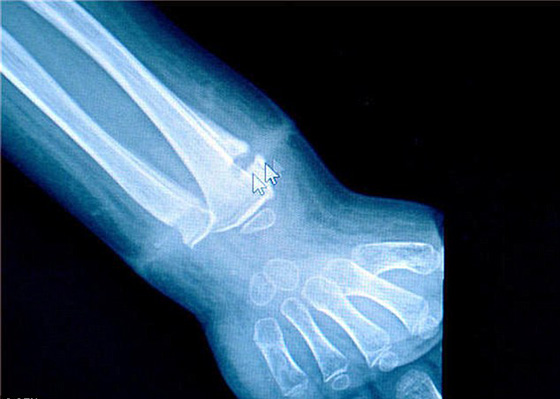

تمكن أطباء من إزالة شريط مطاطي من على معصم صبي صيني بعد أن كان ينمو داخل جلده لعدة سنوات. وكان الطفل على وشك إجراء عملية جراحية لبتر يده من الرسغ، بعد أن اكتشف الأطباء في مستشفى تشانغدو في الصين حالته التي تؤثر على نمو العظام لدى الطفل. وقال الأطباء إن الجسم الغريب حول معصم الطفل يؤثر على نمو عظام الصبي ويقيد حركة ذراعه.

وكانت والدة الطفل قد قدمت له هدية وهي عبارة عن سوار من الفضة حين كان يبلغ من العمر عاما واحدا، كتميمة له لحمايته من الأمراض. إلا أن جدة الطفل خلعت السوار من معصم الطفل في ديسمبر الماضي بعد أن أصبح ضيقا على معصم الطفل. وحال خلع السوار وجدت الجدة آثارا حمراء وانتفاخا حول معصم الصبي، لتتدهور صحة الطفل على إثرها بعد عدة شهور. وكان الأطباء على وشك إجراء عملية جراحية للطفل لبتر يده، إلا أنهم عثروا على الشريط المطاطي حول معصم الطفل مزروع داخل الجلد. ويقول المستشفى إن هذه الحالة ليست معزولة، فقد أحضر طفل إلى نفس المستشفى العام الماضي بعد أن تم ربط سوار أحمر محكم جدا حول معصمه مما أدى إلى بتر أصابعه. وحذر المستشفى من أن على الآباء أن يكونوا أكثر حذرا ومراقبة أبنائهم من أجل التنبه لهكذا مشاكل تحدث مع الأطفال.